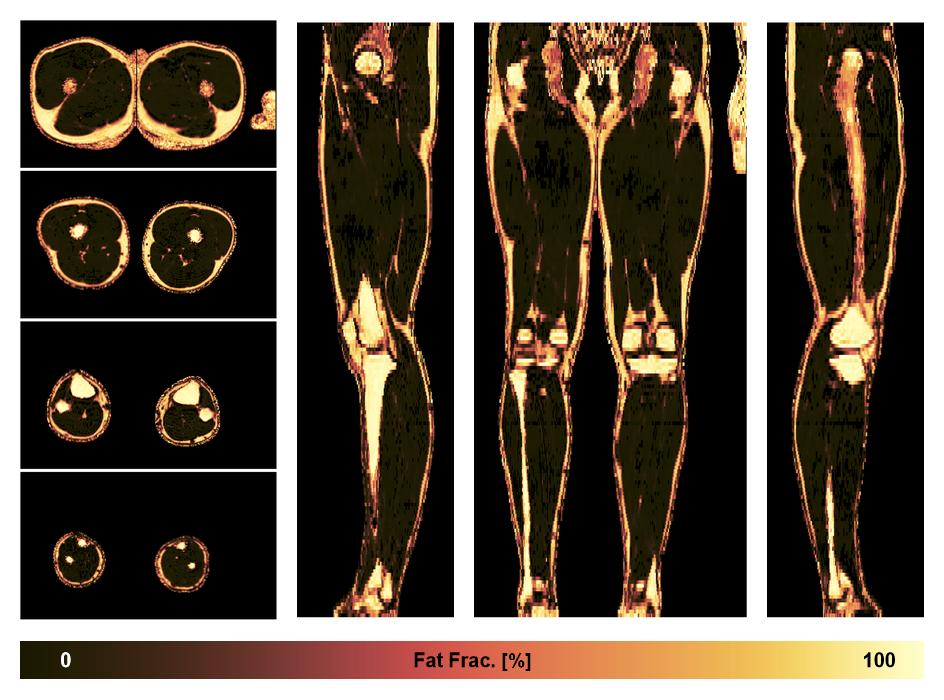

• Fat fraction

The fat fraction of the lower extremity obtained from the dixon reconstruction for muscle water fat quantification.